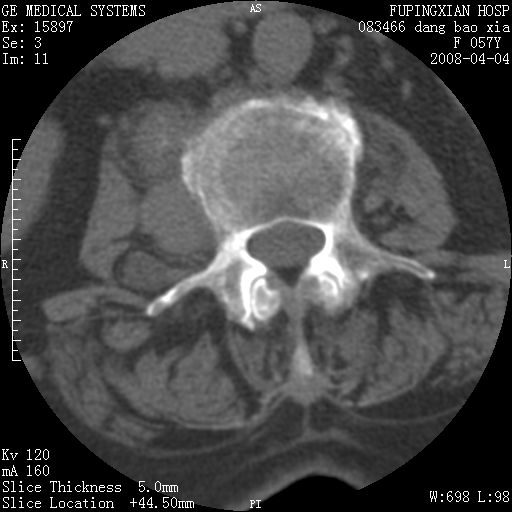

标题: CT12677:女性,57岁,疼痛数月。 [打印本页]

标题: CT12677:女性,57岁,疼痛数月。

椎体及附件骨质破坏同时伴软组织肿块,首先考虑恶性肿瘤。

椎体及附件骨质破坏,伴软组织肿块,首先考虑恶性骨肿瘤,建议提供正侧位片。

骨组织起源,膨胀,软组织肿块=恶性改变:首选骨巨,其次转移瘤,再次脊索瘤

椎体及附件溶骨性破坏,周围巨大软组织肿块,首先考虑转移瘤。